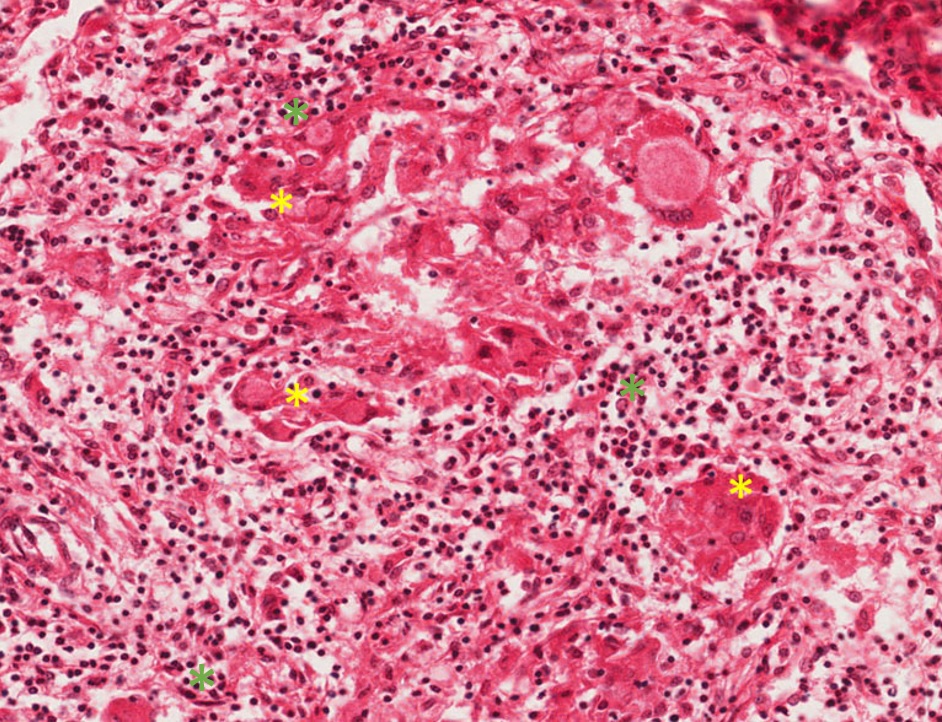

Fragmento de mucosa revestido por tecido epitelial estratificado pavimentoso ceratinizado, apresentando hiperplasia pseudoepiteliomatosa (sensação de que o epitélio “invade” o tecido conjuntivo) e áreas de micro abcessos (pequenas coleções de neutrófilos e piócitos superficiais). No tecido conjuntivo subjacente, observa-se a formação de granulomas (circunscrito pelo tracejado) que apresentam externamente fibroplasia (setas pretas), seguida por um colar de linfócitos (asterisco vermelho), e mais centralmente observam-se um aglomerado de macrófagos epitelióides (asterisco amarelo - núcleo claro e alongado e as células podem apresentar um arranjo em paliçada ou justapostas umas às outras). Entremeados as células do granuloma observam-se células gigantes do tipo Langhans. Em algumas áreas, principalmente no interior das células gigantes, é possível visualizar os fungos que se apresentam como um espaço negativo (branco) e forma geométrica redonda (asterisco verde).

Observar os granulomas compostos por um aglomerado de macrófagos epitelióides, colar de linfócitos e fibroplasia externa assim como a presença de células gigantes fagocitando os fungos. Os microabcessos e a hiperplasia pseudoepiteliomatosa são sugestivos, mas não específicos desta doença.